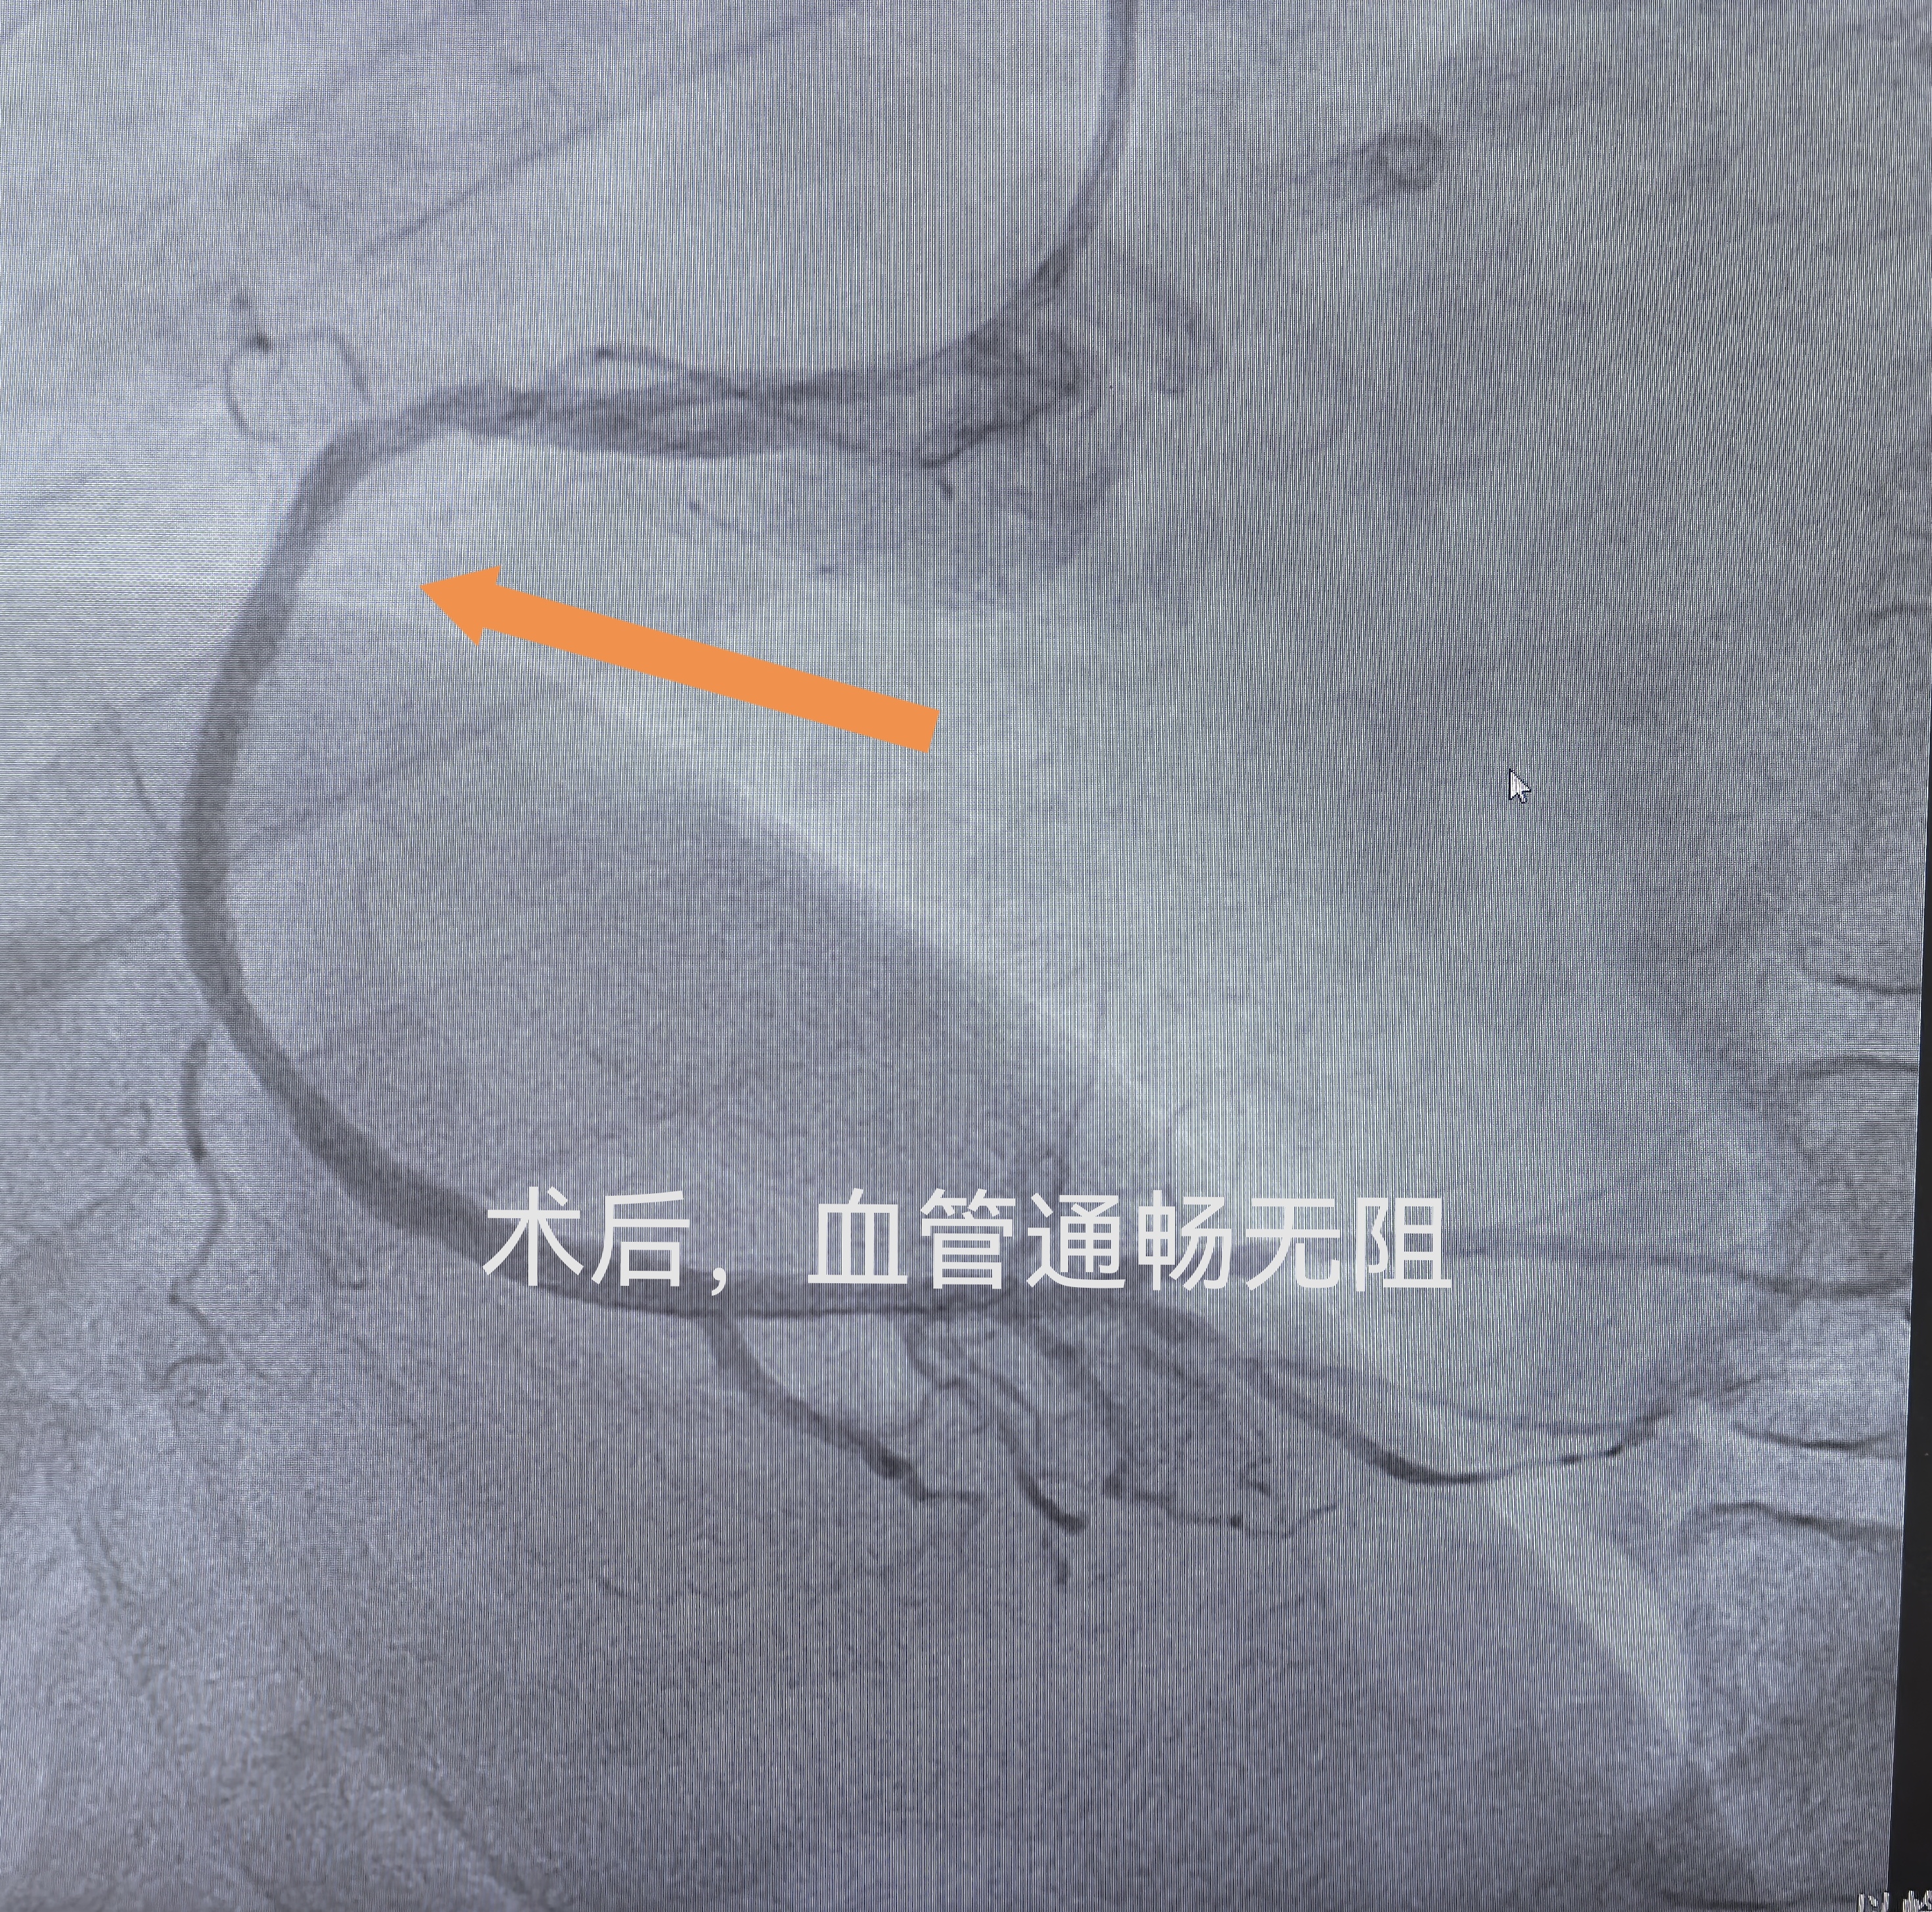

手术中,牛锋主任带领团队精准操作,先清理支架内血栓与增生组织,再将药物球囊精准贴附于病变血管,顺利完成药物释放与血管修复。血管开通的瞬间,患者胸闷、憋闷感立刻缓解,呼吸恢复顺畅。

术后,医院发挥中西医结合特色,为患者制定个性化康复方案。在规范服用抗血小板、调脂、控糖等基础药物的同时,配合通络中药协同调理,帮助修复血管内皮、改善心肌微循环、减轻身体负担,巩固手术疗效,加速心脏康复。经过系统治疗与调理,患者恢复迅速,胸闷、气短、后背酸胀等症状完全消失,精神状态明显好转,不久便顺利出院。